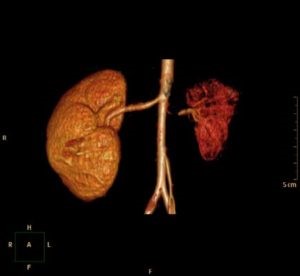

У детей иногда выявляется гипоплазия одной из почек, правой или левой. Это врождённое заболевание, которое не может быть приобретено. Оно проявляется в уменьшении размеров органа из-за недостатка нефронов — клеток, составляющих почку. Хотя орган продолжает функционировать, его эффективность снижается. Вторая, здоровая почка берет на себя большую часть нагрузки, что не отражается на общем состоянии здоровья. Гипоплазия правой почки чаще наблюдается у девочек, чем у мальчиков. Если заболевание обнаружено, но не влияет на качество жизни, то лечение не требуется. Гораздо более серьёзной является двусторонняя почечная гипоплазия, которая может привести к инвалидности.